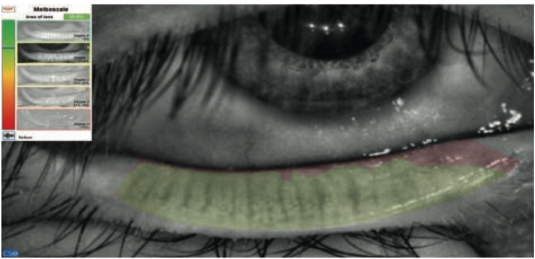

Il VX 205 consente la visualizzazione delle ghiandole di Meibomio con luce infrarossa. La semplice rilevazione dell’area di perdita consente una classificazione automatica basata su una scala di riferimento integrata.